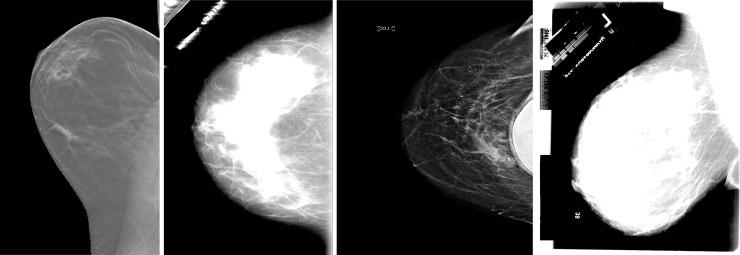

The real cause of breast cancer is very challenging to determine and therefore early detection of the disease is necessary for reducing the death rate due to risks of breast cancer. Early detection of cancer boosts increasing the survival chance up to 8%. Primarily, breast images emanating from mammograms, X-Rays or MRI are analyzed by radiologists to detect abnormalities. However, even experienced radiologists face problems in identifying features like micro-calcifications, lumps and masses, leading to high false positive and high false negative. Recent advancement in image processing and deep learning create some hopes in devising more enhanced applications that can be used for the early detection of breast cancer. In this work, we have developed a Deep Convolutional Neural Network (CNN) to segment and classify the various types of breast abnormalities, such as calcifications, masses, asymmetry and carcinomas, unlike existing research work, which mainly classified the cancer into benign and malignant, leading to improved disease management. Firstly, a transfer learning was carried out on our dataset using the pre-trained model ResNet50. Along similar lines, we have developed an enhanced deep learning model, in which learning rate is considered as one of the most important attributes while training the neural network. The learning rate is set adaptively in our proposed model based on changes in error curves during the learning process involved. The proposed deep learning model has achieved a performance of 88% in the classification of these four types of breast cancer abnormalities such as, masses, calcifications, carcinomas and asymmetry mammograms.

乳腺癌的确切病因很难确定,因此早期发现疾病对于降低乳腺癌死亡率至关重要。癌症的早期发现可以提高 8%的生存率。放射科医生主要通过分析乳房 X 光片、X 光或 MRI 产生的乳房图像来检测异常。然而,即使是经验丰富的放射科医生在识别微钙化、肿块和肿块等特征时也会遇到问题,导致高假阳性和高假阴性。图像处理和深度学习的最新进展为设计更多增强型应用程序带来了一些希望,这些应用程序可用于早期发现乳腺癌。在这项工作中,我们开发了一种深度卷积神经网络(CNN),用于分割和分类各种类型的乳房异常,如钙化、肿块、不对称和癌,与现有的主要将癌症分为良性和恶性的研究工作不同,这可以改善疾病管理。首先,我们在自己的数据集上使用预训练模型 ResNet50 进行了迁移学习。类似地,我们开发了一种增强型深度学习模型,其中学习率被认为是训练神经网络时最重要的属性之一。在我们提出的模型中,根据学习过程中误差曲线的变化自适应地设置学习率。所提出的深度学习模型在对肿块、钙化、癌和不对称乳房 X 光等四种乳腺癌异常类型的分类中取得了 88%的性能。